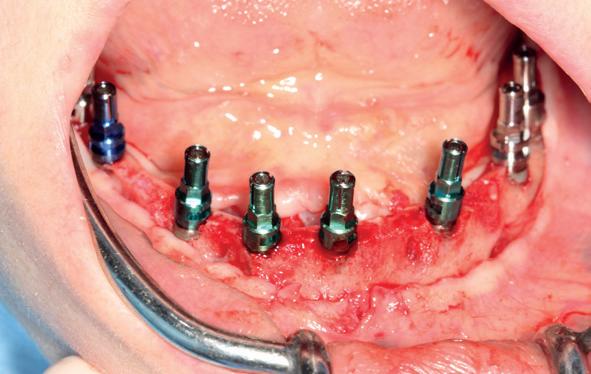

Tijdens de chirurgische behandeling worden na het afschuiven van de flap de posities bepaald van de implantaten met de boorsjabloon. In de bovenkaak worden 7 implantaten geplaatst en in de onderkaak 8

implantaten geplaatst terwijl in de zijdelingse delen voor een bredere diameter (3,75 & 4,1) is gekozen, met lengte 8,5 en 10mm.

5. Implantaten geplaatst op geleide van een boorsjabloon; botopbouw met sinuslift volgens de GBR-techniek en Caldwell Luc methode; materialen: Oragraft & BioOss, Ossix membr, hyaluronzuur. In de BK is gekozen voor Bego implantaten (Bego SC en RSX 3,75x 11,5 & 13mm).

6. In het front zijn Bego 3,25mm